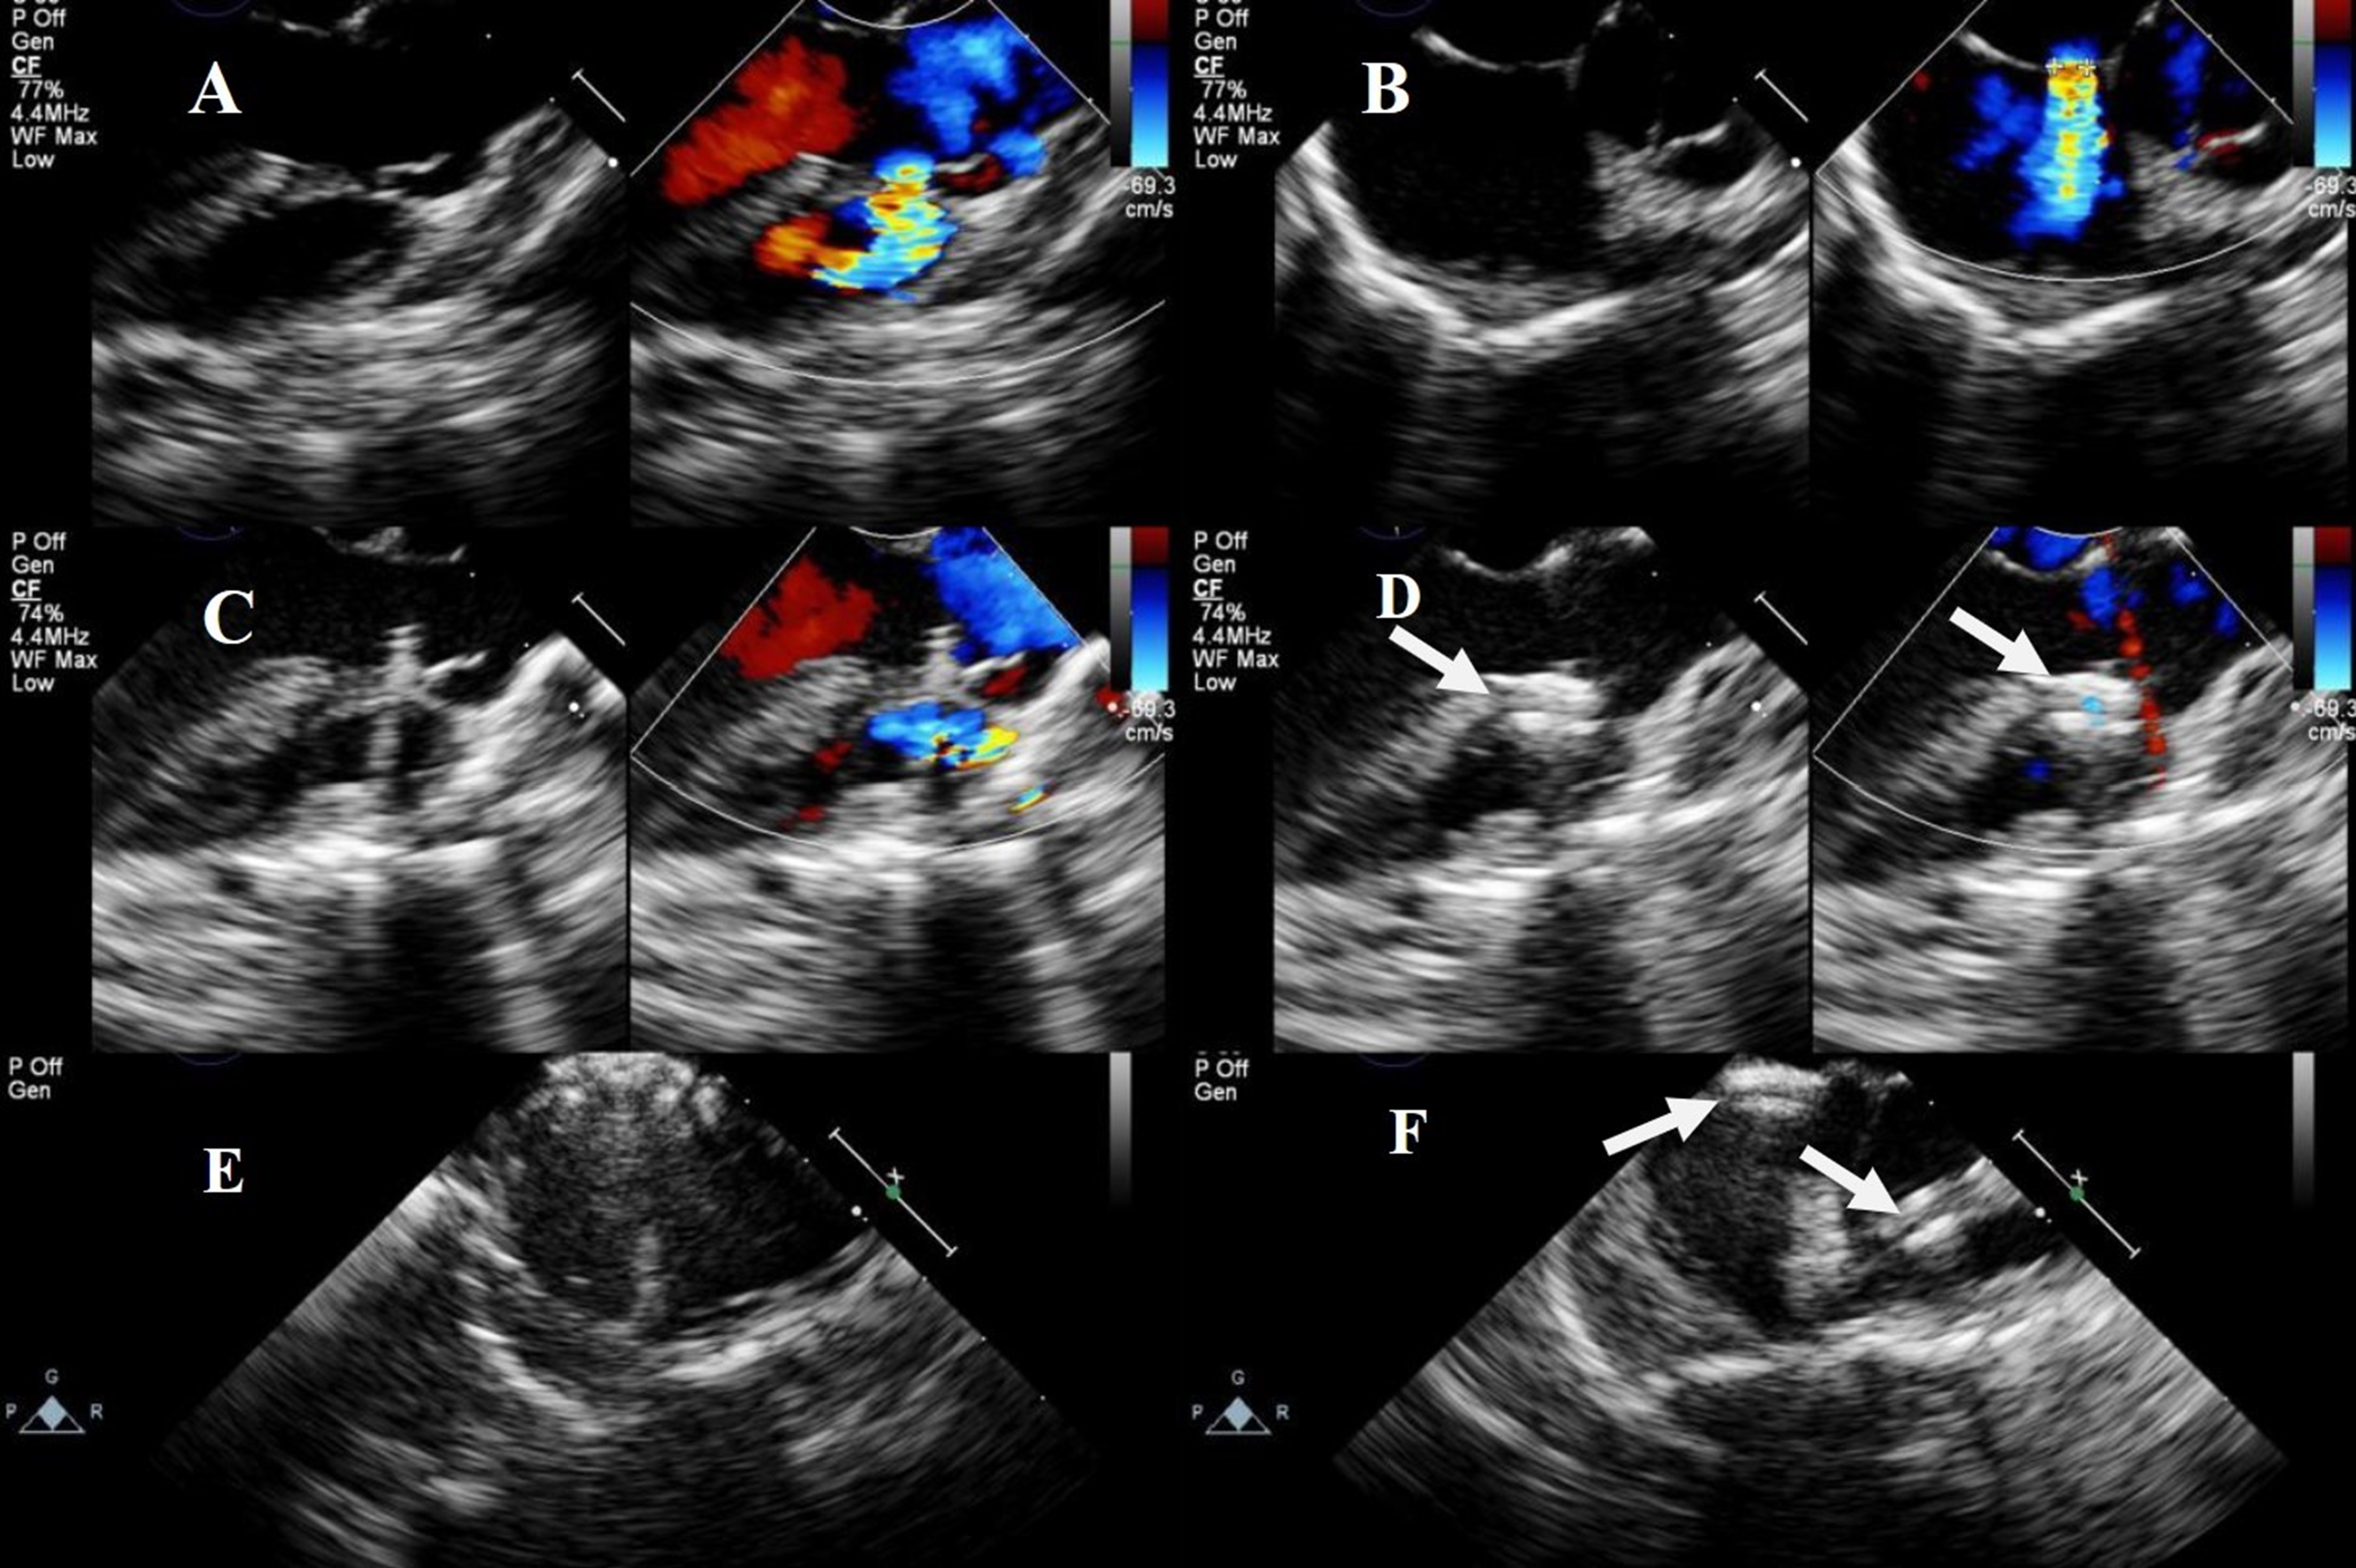

(2) Combined left parasternal–perventricular and percutaneous approaches

For DCVSD and PmVSD with a shunt directed towards the pulmonary valve, the left parasternal perventricular approach was used for occlusion, followed by ASD occlusion via the femoral vein. The procedure begins by making a 2–3 cm incision in the second or third intercostal space along the left sternal edge, directing the pericardial incision towards the right ventricular outflow tract. After opening and suspending the pericardium, a puncture point was selected on the surface of the right ventricle, and a double-layer purse-string suture was placed around the puncture point. Then, the right ventricular outflow tract was punctured within the purse-string suture, and the VSD occlusion was completed. Afterward, the ASD occlusion was achieved via the femoral vein route. Fig. 5 illustrates the steps for device closure of a DCVSD with an ASD.

Fig. 5. Transesophageal echocardiography of combined left parasternal–perventricular and percutaneous approaches. (A) Shunt flow of visible DCVSD. (B) shunt flow of visible ASD. (C) Delivery sheath passing through DCVSD. (D) Successful occlusion of DCVSD. (E) ASD occluded via a catheter. (F) Successful occlusion of both DCVSD and ASD. Note: arrow = occluder.